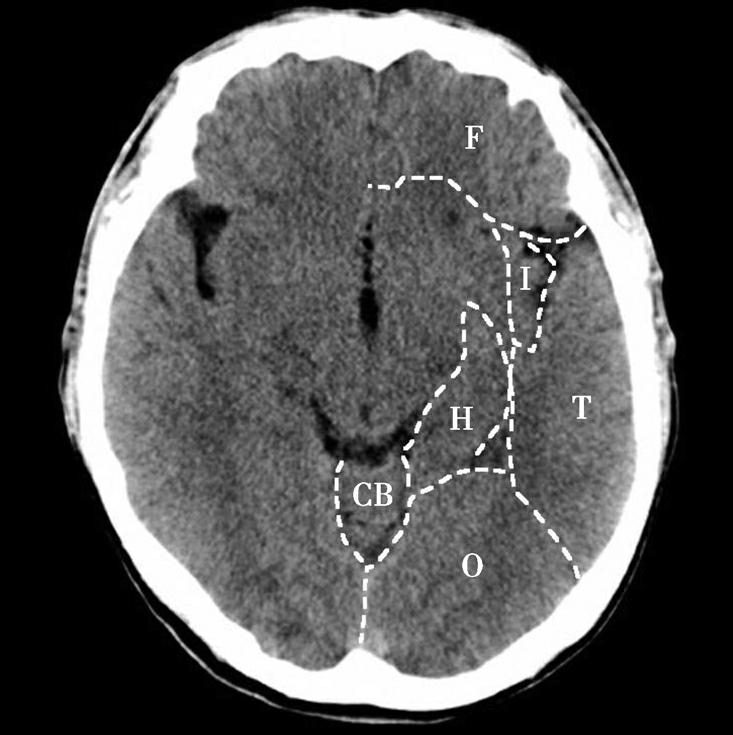

图1-2-23 脑叶划分示意图

CB.小脑;T.颞叶;F.额叶;O.枕叶;H.海马回及海马结构;I.岛叶

中脑位居此层面的中央,其腹侧可见两侧大脑脚,大脑脚底有黑质与红核,中脑背侧可见左右稍隆起者为上丘,上丘后方为四叠体池,中脑顶盖的前方可见中脑导水管断面呈针孔样,中脑外侧为环池,中脑前方中间为第三脑室下部。第三脑室下部两前外侧有尾状核头及豆状核壳部,尾状核头及壳核部分相连,壳核的外侧为屏状核、岛叶及外侧裂池,再外侧为颞盖,其前部为颞上回,后部为颞中回。外侧裂池分隔前方的额叶和后方的颞叶,可作为区分额叶与颞叶的重要标志。四叠体池后方有小脑上蚓及两侧呈倒“八”字形的小脑天幕,天幕后方为直窦和上矢状窦。